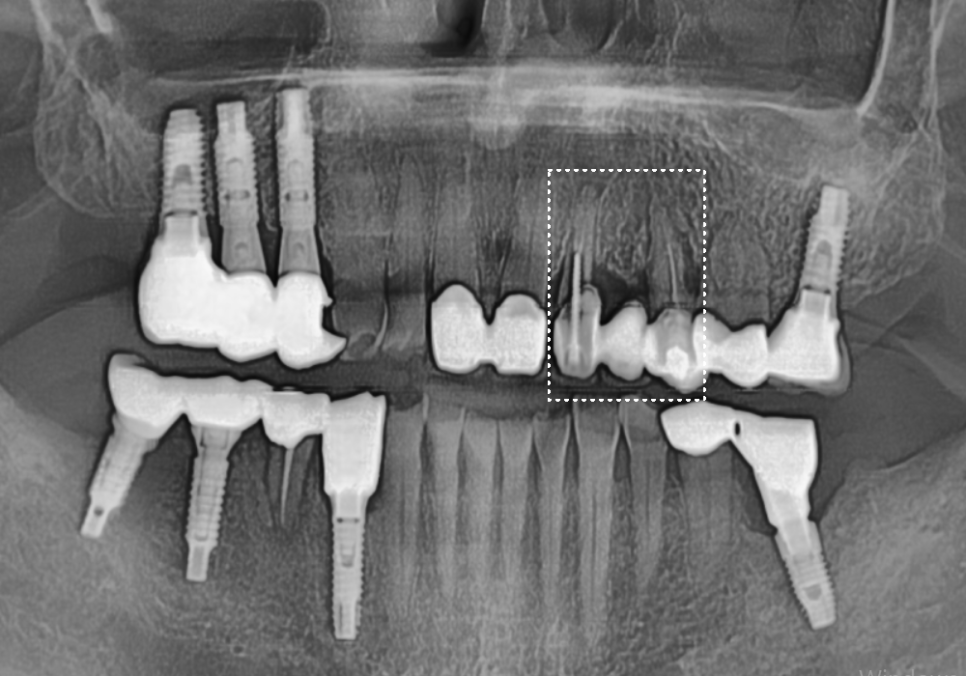

231011

방사선 사진을 확인하니

치아 뿌리 끝에 염증이 크게 번져

주변 잇몸뼈를 많이 녹인 상태였습니다.

결국 발치 후 뼈이식을 동반한

임플란트 수술이 불가피했죠.